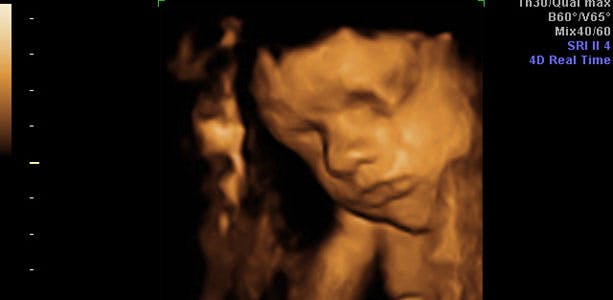

Gravid uge 28: Mærker liv hver dag

Undersøgelser viser, at din baby kan drømme, og man mener at det endda har evnen til at mindes også. Baby stiller også større krav til din krop, og kontakten bliver mere intensiv. For eksempel kan baby reagere med spark tilbage, hvis du puffer til maven. I slutningen af ugen måler din baby cirka 35 cm og vejer cirka 1200 gram. Maveomkredsen er cirka 24,5 cm, lårbenet cirka 5,3 cm og hovedet cirka 7,2 centimeter.